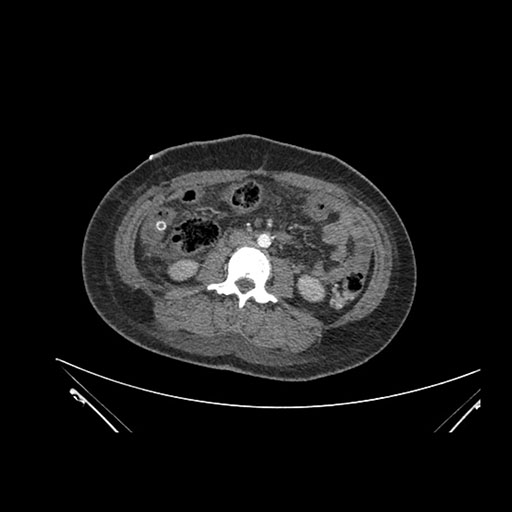

Imaging Analysis

Look through the patient's CT scan to identify any areas of concern for the necessary procedure.

Axial Venous